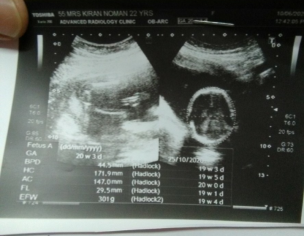

Aoa. Dr mera abhi kuch din phly anomaly scan huwa ha sonographer kh rahe the k baby bohat neachy ha mujhe Bethany mn bohat masla hota ha washroom mn bethna bohat mushkil ho jata ha left side pr lower abdomen mn dabao parta ha bethty waqt or lower abdomen mn halka halka khichao rehta ha har dr available nai ha abhi kindly guide kar dain k mujhe Kia Karna chahye. Anomaly scan ki report attach ha sath. Thanks

anomaly scan is normal-u better do ur urine RE and then can hv OBG consultation...